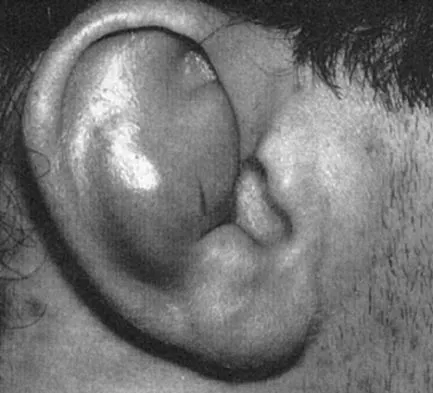

Question 66High Yield

A 32-year-old woman with systemic lupus erythematosus treated with methotrexate and oral corticosteroids reports right groin pain with ambulation and night pain. Examination reveals pain with internal and external rotation and flexion that is limited to 105 degrees because of discomfort. Laboratory studies show a serum WBC of 9.0/mm3 and an erythrocyte sedimentation rate of 35 mm/h. Figures 5a and 5b show AP and lateral radiographs of the right hip. Further evaluation should include

Explanation